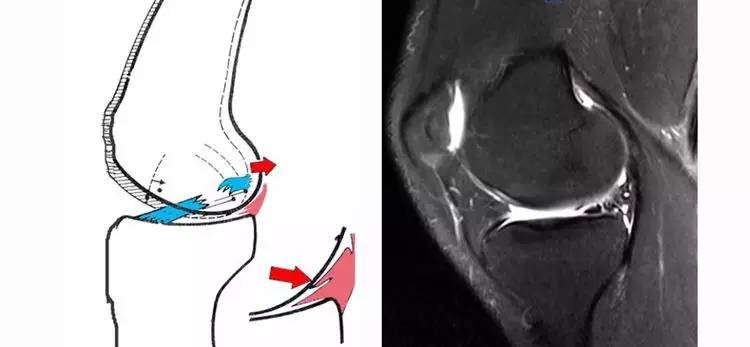

3.接吻征:膝关节过伸受伤时,胫骨前部撞击股骨髁前部,形成对称性骨挫伤;如果同时有一外翻力的话,膝关节外侧可出现对称性挫伤,这种对称性骨挫伤称为接吻征。也有人把轴移造成的股骨外侧髁和胫骨外后方水肿称为接吻征。

16.gif

4.Segond骨折:胫骨平台前外侧撕脱骨折(胫骨平台腓骨尖上方,关节线下方的撕脱骨折),多因为下肢过度内翻加内旋暴力所致。骨折本身无特殊治疗。但其强烈提示ACL损伤(75–100%)。

17.jpg